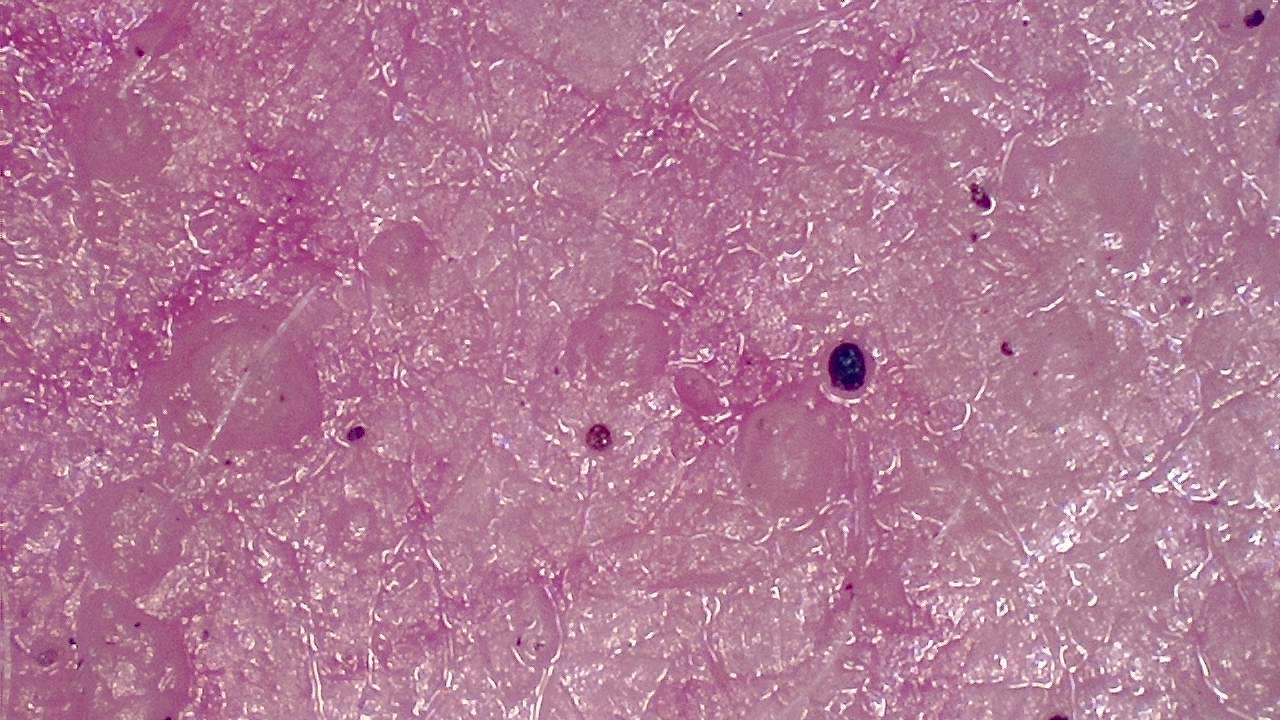

bloed

stromend door de huid (video) |